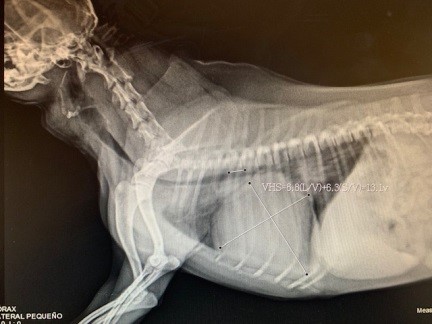

Hace ya algunos años llego a nuestra clínica Happy Pets “Camila” una linda perrita Schnauzer con falta de interés en la comida, abdomen distendido, falta de energía latidos rápidos y tos severa, tras una evaluación clínica minuciosa, se determinó que presentaba una enfermedad cardiaca, la cual pudimos confirmar con exámenes complementarios como radiografía y electrocardiograma, la enfermedad de Camila se llama ICC (insuficiencia cardiaca congestiva).

Cuando el corazón empieza a fallar, el organismo puede compensar para asegurarse que los tejidos reciban la sangre y el oxígeno que necesitan. Cuando el corazón es incapaz de bombear cantidades adecuadas de sangre, se acumula líquido en el cuerpo, causando congestión. En caso de darse insuficiencia del lado izquierdo del corazón, se retiene líquido en los pulmones. En la insuficiencia cardíaca del lado derecho del corazón, el líquido se acumula en el abdomen.